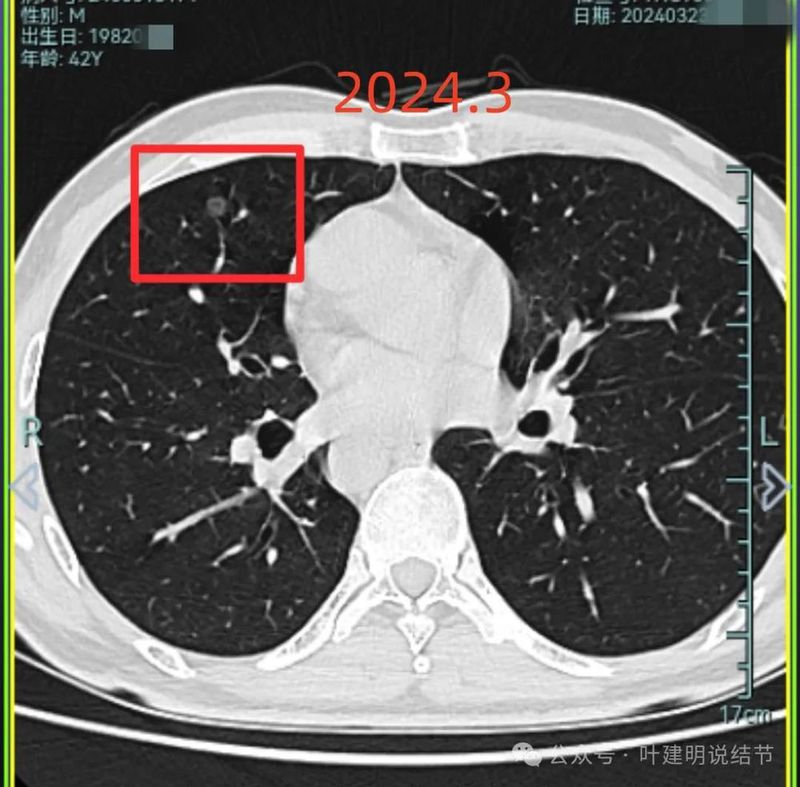

2024年3月右侧病灶仍无明显两样。

右中叶与左上叶的都考虑是肿瘤范畴的,对比其实2019年时就有,红色的是右中叶的,没有显著进展变化,考虑原位癌可能性较大;桔色的是左上叶的,略有进展,考虑慢性炎伴肺泡上皮不典型增生或肺泡上皮增生可能性大,近期风险仍不算大,我觉得可以先常规年度复查随访,若有进展再考虑干预处理,可楔形切除的。意见供参考!